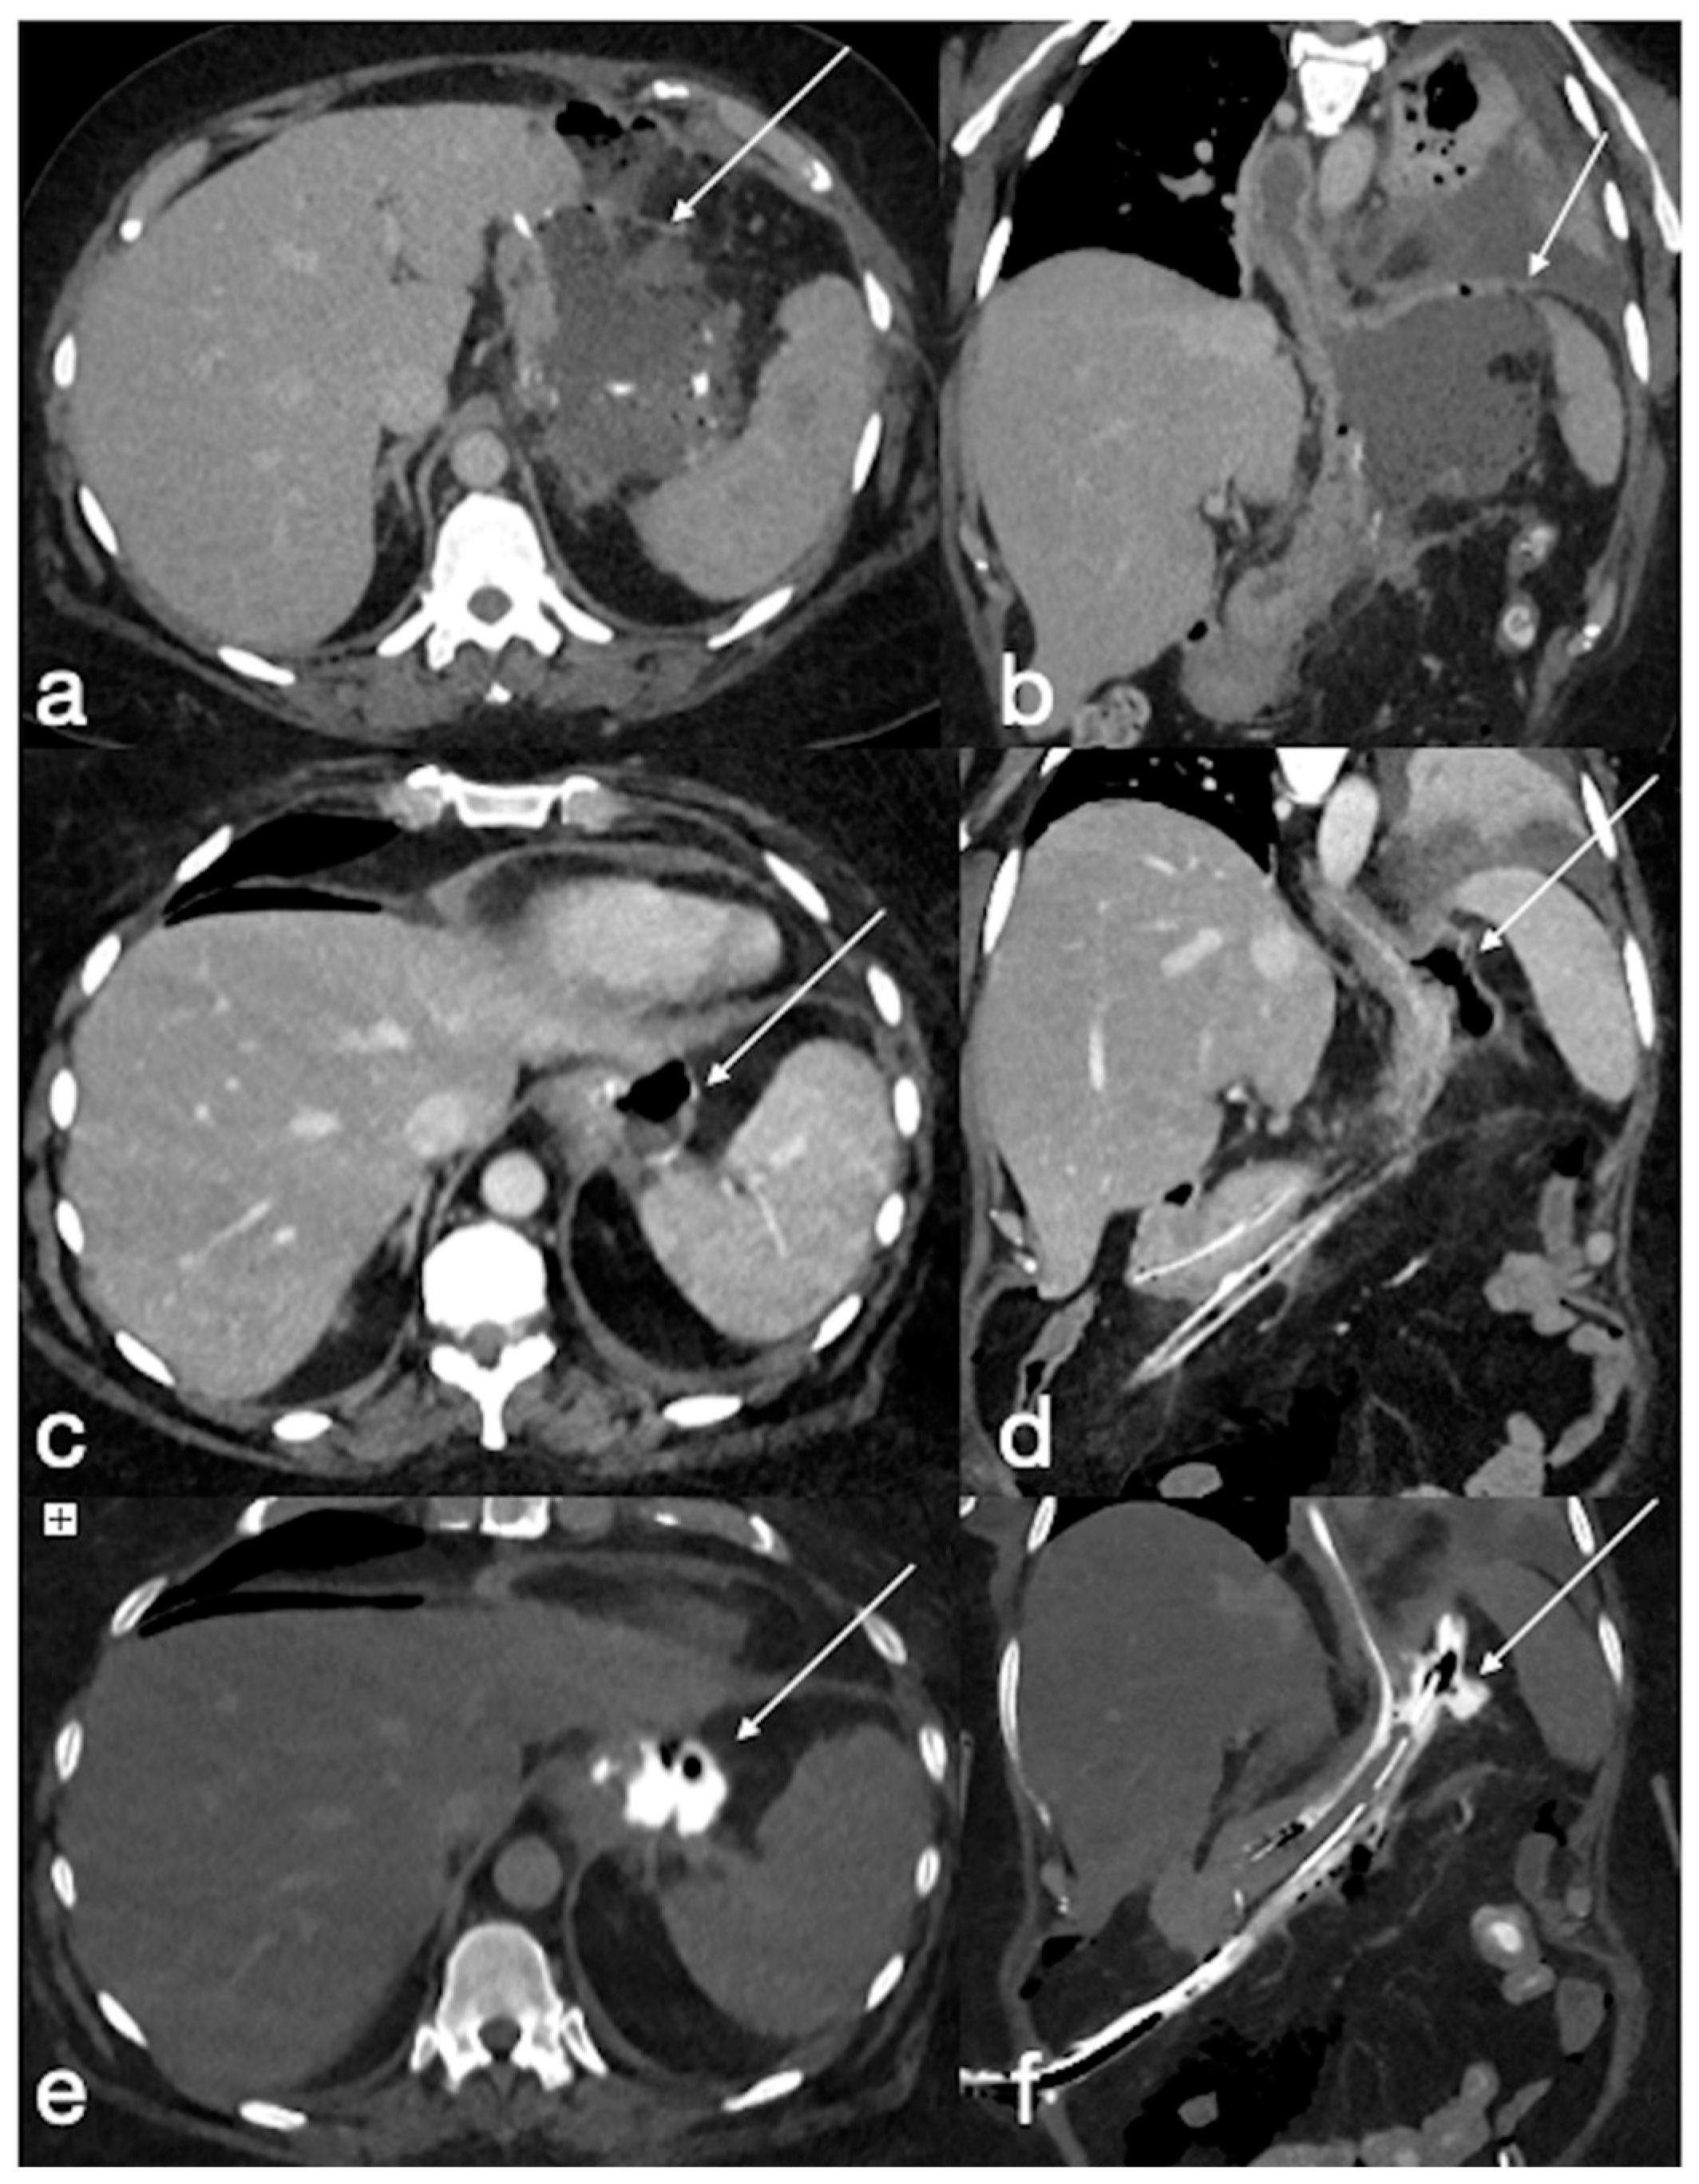

Figure 13. Type III leak after sleeve gastrectomy (a, axial, b, coronal oblique view, arrows) requiring surgical re-suturing. Eight days later, the CT again showed an air–fluid collection adjacent to the proximal gastric suture (c, axial, d, coronal oblique view, arrows) with extraluminal spreading of oral contrast medium (e, axial, f coronal oblique view, arrows). After any attempt at conservative treatment, the patient underwent total gastrectomy.